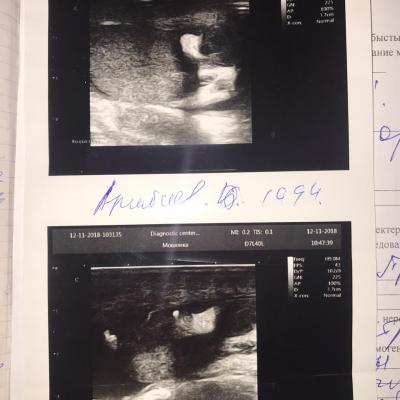

у меня ещё осталось восполнения яичка слева

Здравствуйте! Судя по результатам УЗИ - мочевой пузырь имеет циллиндрическую форму, имеется пиелоэктазия с обеих сторон, что свидетельствует о нарушении уродинамики . Надо сделать анализ крови на креатинин и сделать мультиспиральную компьютерную томографию почек, мочеточников, мочевого пузыря, простаты.(с контрастом). Присылайте результаты, проконсультируем. Удачи!